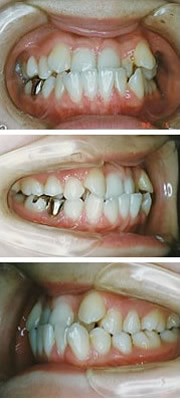

矯正装置には、取り外しのできる装置と口の中に入ったままの固定式装置があります。固定式装置には、歯の表側につけるものと、歯の裏側につけるものがあります。

| ●固定式装置 | ●歯の表側のもの |

| ●歯の裏側のもの | |

矯正装置は、症状によって決定します。一般には歯の表面に銀色の装置をつけると思われがちですが、他の方法もありますので、矯正治療をするのが恥ずかしいということはありません。